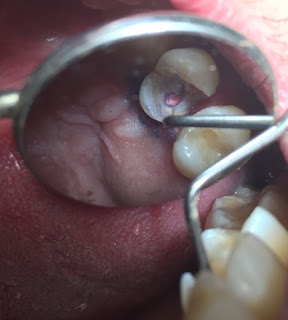

APERTURA CAMERAL

•Localización y permeabilización de las entradas de los conductos radiculares

•Facilitar el ingreso al conducto

•Pieza de alta velocidad

•Fresas de alta velocidad (Especialmente fresas redondas)

PULPECTOMIA

Extirpación de la pulpa dental (Cámara y conductos)

•Se realiza con tiranervios y limas